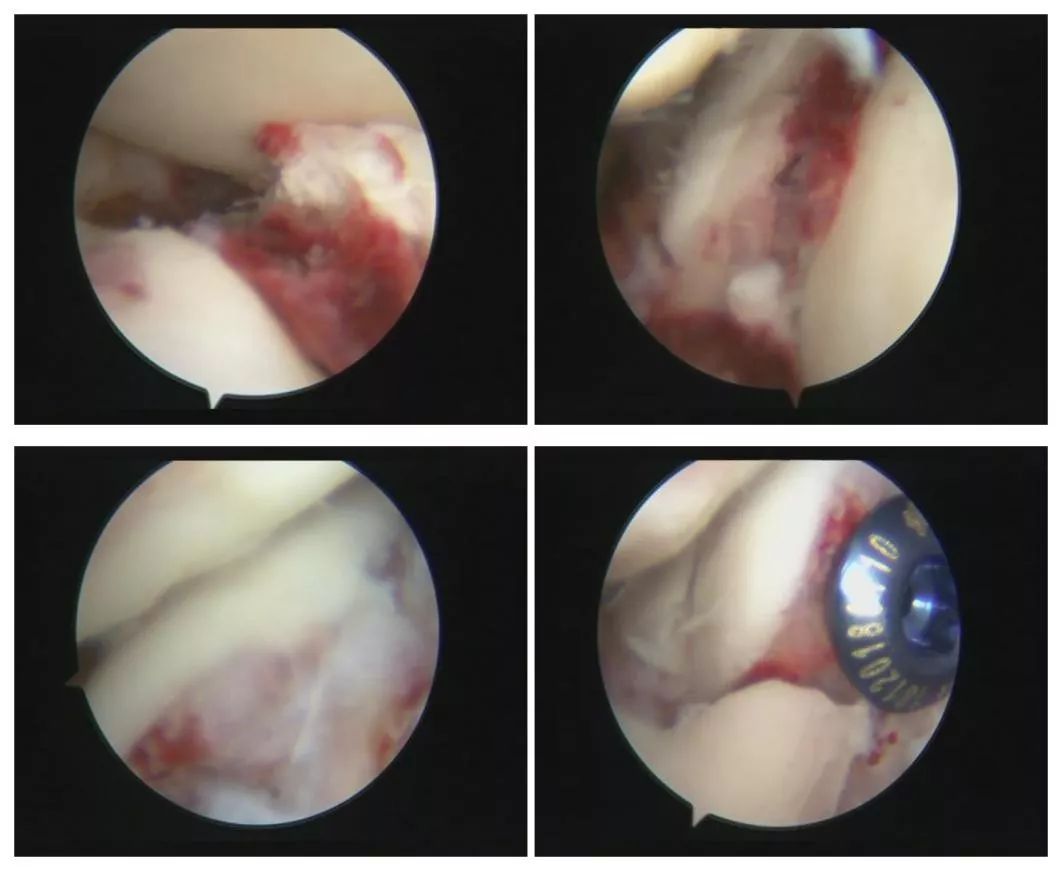

桂主任经过深思熟虑以及个体化分析后决定,没有“腔隙”,咱就“造”一个“腔隙”。通过独创的“关节镜下定点有限造腔微创关节镜全直视下精准复位技术”。

桂教授团队完美的通过

数个0.5cm长的小切口

将移位的骨块精准复位

并通过螺钉牢固固定

手术仅历时60分钟

全部手术均在关节镜直视下完成

桂主任介绍,以往临床上通常采用关节镜技术来治疗跟骨骨折,但仅用于监控关节面的复位效果,不能做到全关节镜直视下复位。桂鉴超教授团队通过多点多方位关节镜下显露技术,360度清晰显露骨折线和关节面,取得关节面的精准解剖复位;再通过关节镜下定点造腔有限显露骨折线,全直视下清理骨折线和断端,轻松达到大切口手术才能完成的精准复位效果;由于是定点有限显露,通过关节镜技术到达窄小的空间,无需切开皮肤和皮下组织,因此创伤小,不会出现皮肤坏死和钢板外露的并发症。